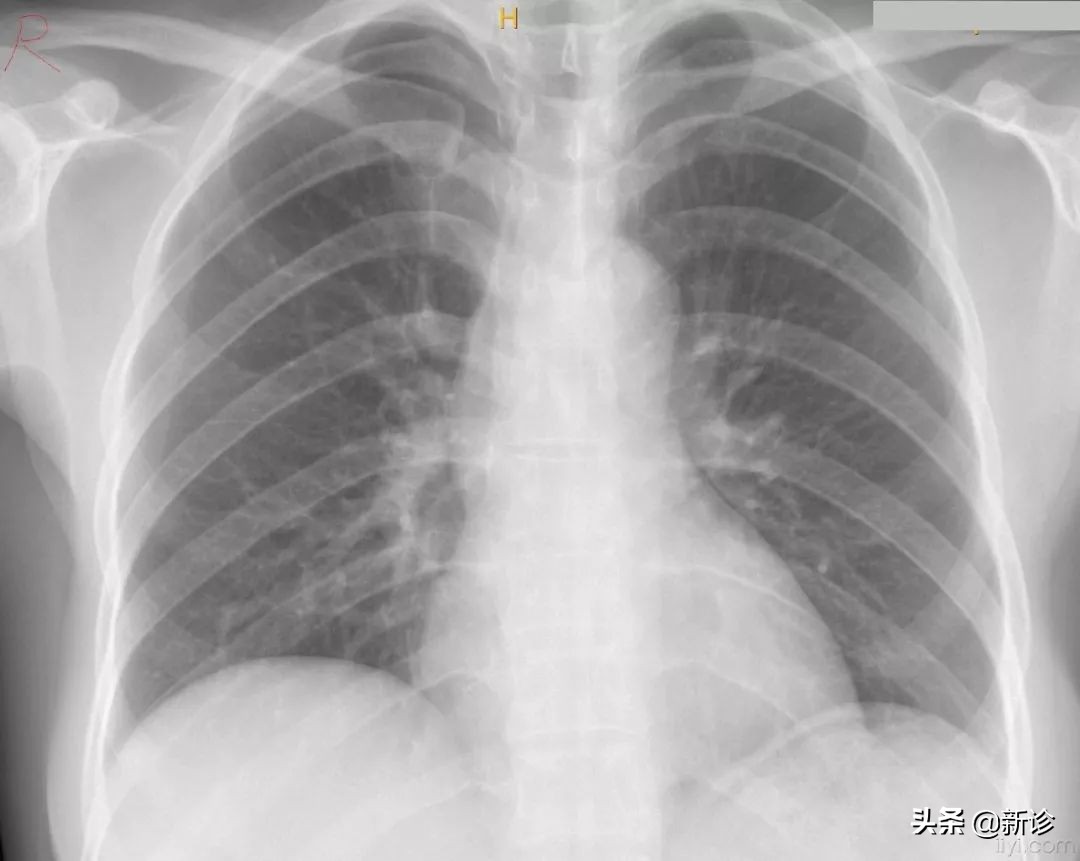

事实上,如果在孕期拍一次X胸片,不能作为流产的指征。

放射线一般对孕早期的胎儿影响更加明显,而孕中晚期的胎儿影响较弱,但就总体来讲,抛开剂量谈辐射,都是耍流氓~~

X光对胚胎所产生的不良影响是存在阈值的!!!

意思就是,接触了X光并不意味着胎儿一定会受到伤害,只有当辐射到了一定的程度,才会出现损伤。

美国妇产科协会(ACOG)在2017年发布了指南,明确指出:只要涉嫌剂量不超过50mSV,就不会对胎儿产生损伤。

那50mSV又是个什么概念的,大概相当于你做6次胸部CT,25次脑部CT,2500次胸片,5000次牙片......

所以偶尔一次胸片或是CT,其实并不会对胎儿产生什么不利影响。

更何况现在的医院越来越人性化,基本都会对接受检查的患者进行一定的防护,孕妇更是可以用铅衣护住小腹和下身。

所以,各位孕妈实在不需要因为孕期偶然接受一次X光检查而心惊胆战、焦虑烦躁,放松心情,您的宝宝一定会健健康康哒,您就放一百个心吧~~